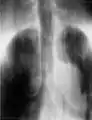

Radiografía

En este segmento de las imágenes médicas se puede encontrar desde los más simples exámenes de Rayos X hasta estudios complejos como el sistema digestivo. Las imágenes son obtenidas gracias a las diferentes capacidades que poseen los tejido de atenuar las radiaciones x, han sido utilizados en el ámbito médico desde su descubrimiento en 1895 por Wilhelm Conrad Röntgen y hasta nuestros días son ampliamente utilizados para realizar diagnósticos diferenciales en el área de la traumatología (pesquisa de fracturas, alteraciones de los huesos y malformaciones), a la vez permiten visualizar algunos órganos de menor densidad como los pulmones, en cuyo caso es posible detectar diferentes patologías que afectan a este órgano cono es el caso de la acumulación de polvos que al ser inhalados causan enfermedades definidas como silicosis. Todo estudio radiográfico está compuesto, a lo menos, por dos proyecciones lo que permite visualizar la estructura estudiada en dos planos perpendiculares.

Este método de adquisición de imágenes puede ser asociado con el uso de medios de contrastes, hidrosolubles sobre la base de bario o yodo dependiendo de la vía de administración, los que permiten realizar estudios específicos del sistema digestivo, urinario lo cual facilita el diagnóstico de una gran variedad de patologías. Desde su descubrimiento hasta la actualidad son muchas las transformaciones que han afectado a los equipos utilizados para tomar radiografías, todas ellas tendientes a reducir de manera considerable la exposición a radiaciones ionizantes tanto de los profesionales (médicos y tecnólogos médicos) que obtienen las imágenes, como la irradiación a la cual está expuesto el pacientes. En los últimos años, con la llegada de los equipos digitales, las dosis de radiación utilizadas para obtener un mismo examen se han reducido de manera considerable (la primera radiografía de una mano que se obtuvo demoró casi 15 minutos de exposición, hoy el mismo examen puede ser adquirido con apenas 20 a 30 milisegundos de exposición) lo que puede implicar una reducción de dosis considerable que podría llegar a ser más de 1000 veces menor.